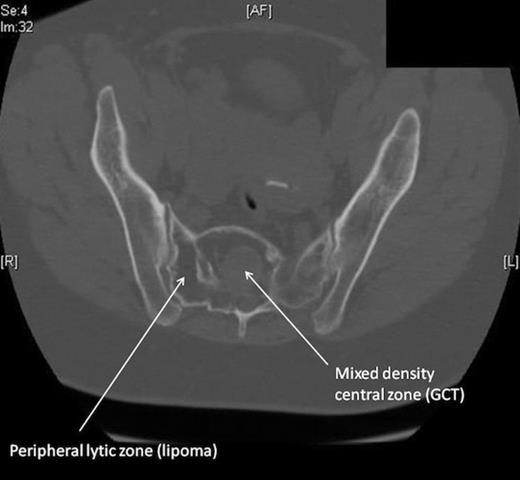

Blood tests including full blood count, urea & electrolytes and inflammatory markers were normal. The patient underwent plain radiographs, MRI and CT scans of the lumbar spine and pelvis. Plain radiographs of the spine and pelvis were normal. The MRI scan (fig. 1) revealed a heterogeneous mass within the proximal sacrum (high signal on T2-weighting), occupying the midline and extending to the sacral ala on the right side, measuring approximately 5x6 cm. Within this lesion was a 3cm area of abnormal low signal towards the midline of the sacrum. The lesion was in close proximity to the exiting right S1 and S2 nerve roots. The CT scan of the pelvis (fig. 2) confirmed the presence of a lytic lesion in the sacrum containing a smaller focus of different signal intensity.

This 58 year old female presented with acute-on-chronic low back pain with features of neurological compromise. Our patient’s presentation of diffuse low back pain with radiation to the lower limb is typical of degenerate disc disease but could also be seen in a sacral GCT. MRI revealed a mass within the sacrum consisting of two distinct parts: a peripheral high-signal area and a central low-signal area. The high intensity signal (on T2-weighting) was characteristic of fatty tissue. Radiographically, the central area was in keeping with a giant cell tumour (GCT), although typically these tend to occur eccentrically rather than in the midline. GCTs are low signal intensity on T1 and T2-weighted images, relating to the haemorrhagic and fibrotic components of the tumour (1). Histology revealed multinucleated cells, characteristic of the giant cells (resembling osteoclasts) that are pathognomic of GCT.